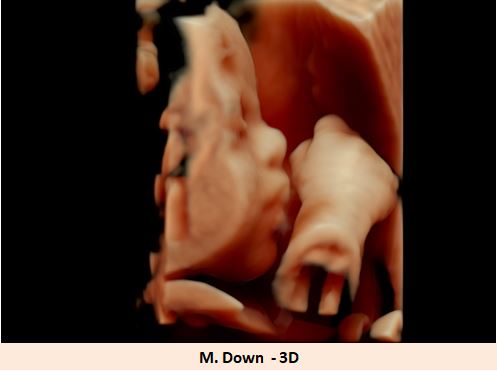

Downův syndrom

patří mezi nejznámější syndromy způsobené chromozomální aberací. V klasické formě je způsoben trizomií chromozomu 21. Je nejčastější vrozenou příčinou mentální retardace. Charakteristickými znaky jsou typický vzhled a srdeční vady .

Na patogenezi Downova syndromu se podílejí jak kódující, tak nekódující sekvence chromozomu 21 a dále také komplexní interakce těchto sekvencí s ostatními geny.